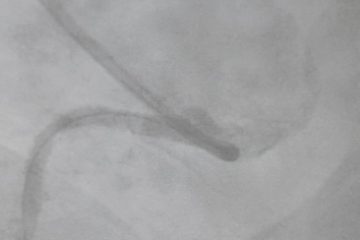

Caso clínico: Realización de  ACTP a la arteria CD

Masculino 70 años sin antecedentes médicos conocidos. Cuadro de IAM en diciembre 2018 sin terapia de reperfusión. Se decide realizar ACTP a la arteria CD. Se logra pasar filamento guía hasta región distal de la CD y posterior a angioplastía de la lesión se deciden colocar 2 stents en el sitio de la obstrucción. MBS...